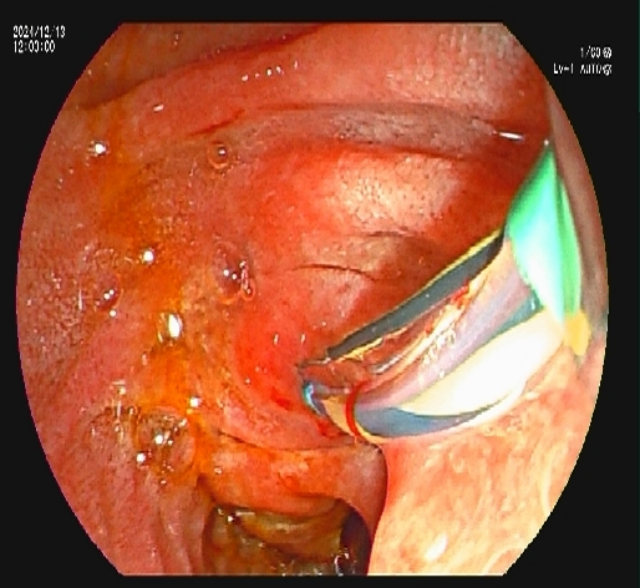

内镜下胰管支架植入术

经全科讨论后,决定为游大爷实施内镜下胰管支架植入术。李春桃主治医师向游大爷及其家属讲解了相关病情及治疗方案,取得同意后在全麻下为其实施了内镜下十二指肠乳头肌切开术(ECT)+内镜逆行胰胆管造影(ERCP)+胰管支架植入术。